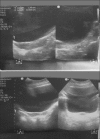

Turner's syndrome is a disorder in females characterized by the absence of all or part of a normal second sex chromosome. It is typically characterized by the combination of physical features and cytogenetics in females. Physical features include short stature, primary amenorrhea, hypogonadism, low hair line at the back of the neck, and digital anomalies. Most affected patients have a 45XO monosomy, but the presence of an abnormal chromosome or mosaicism of 45X with another cell line can also fulfill the criteria. Features seen in the oral cavity of patients diagnosed with Turner's syndrome include high palatal vault, hypoplastic mandible, prematurely erupting teeth, and orthodontic anomalies. A case of Turner's syndrome with localized aggressive periodontitis has been reported here.